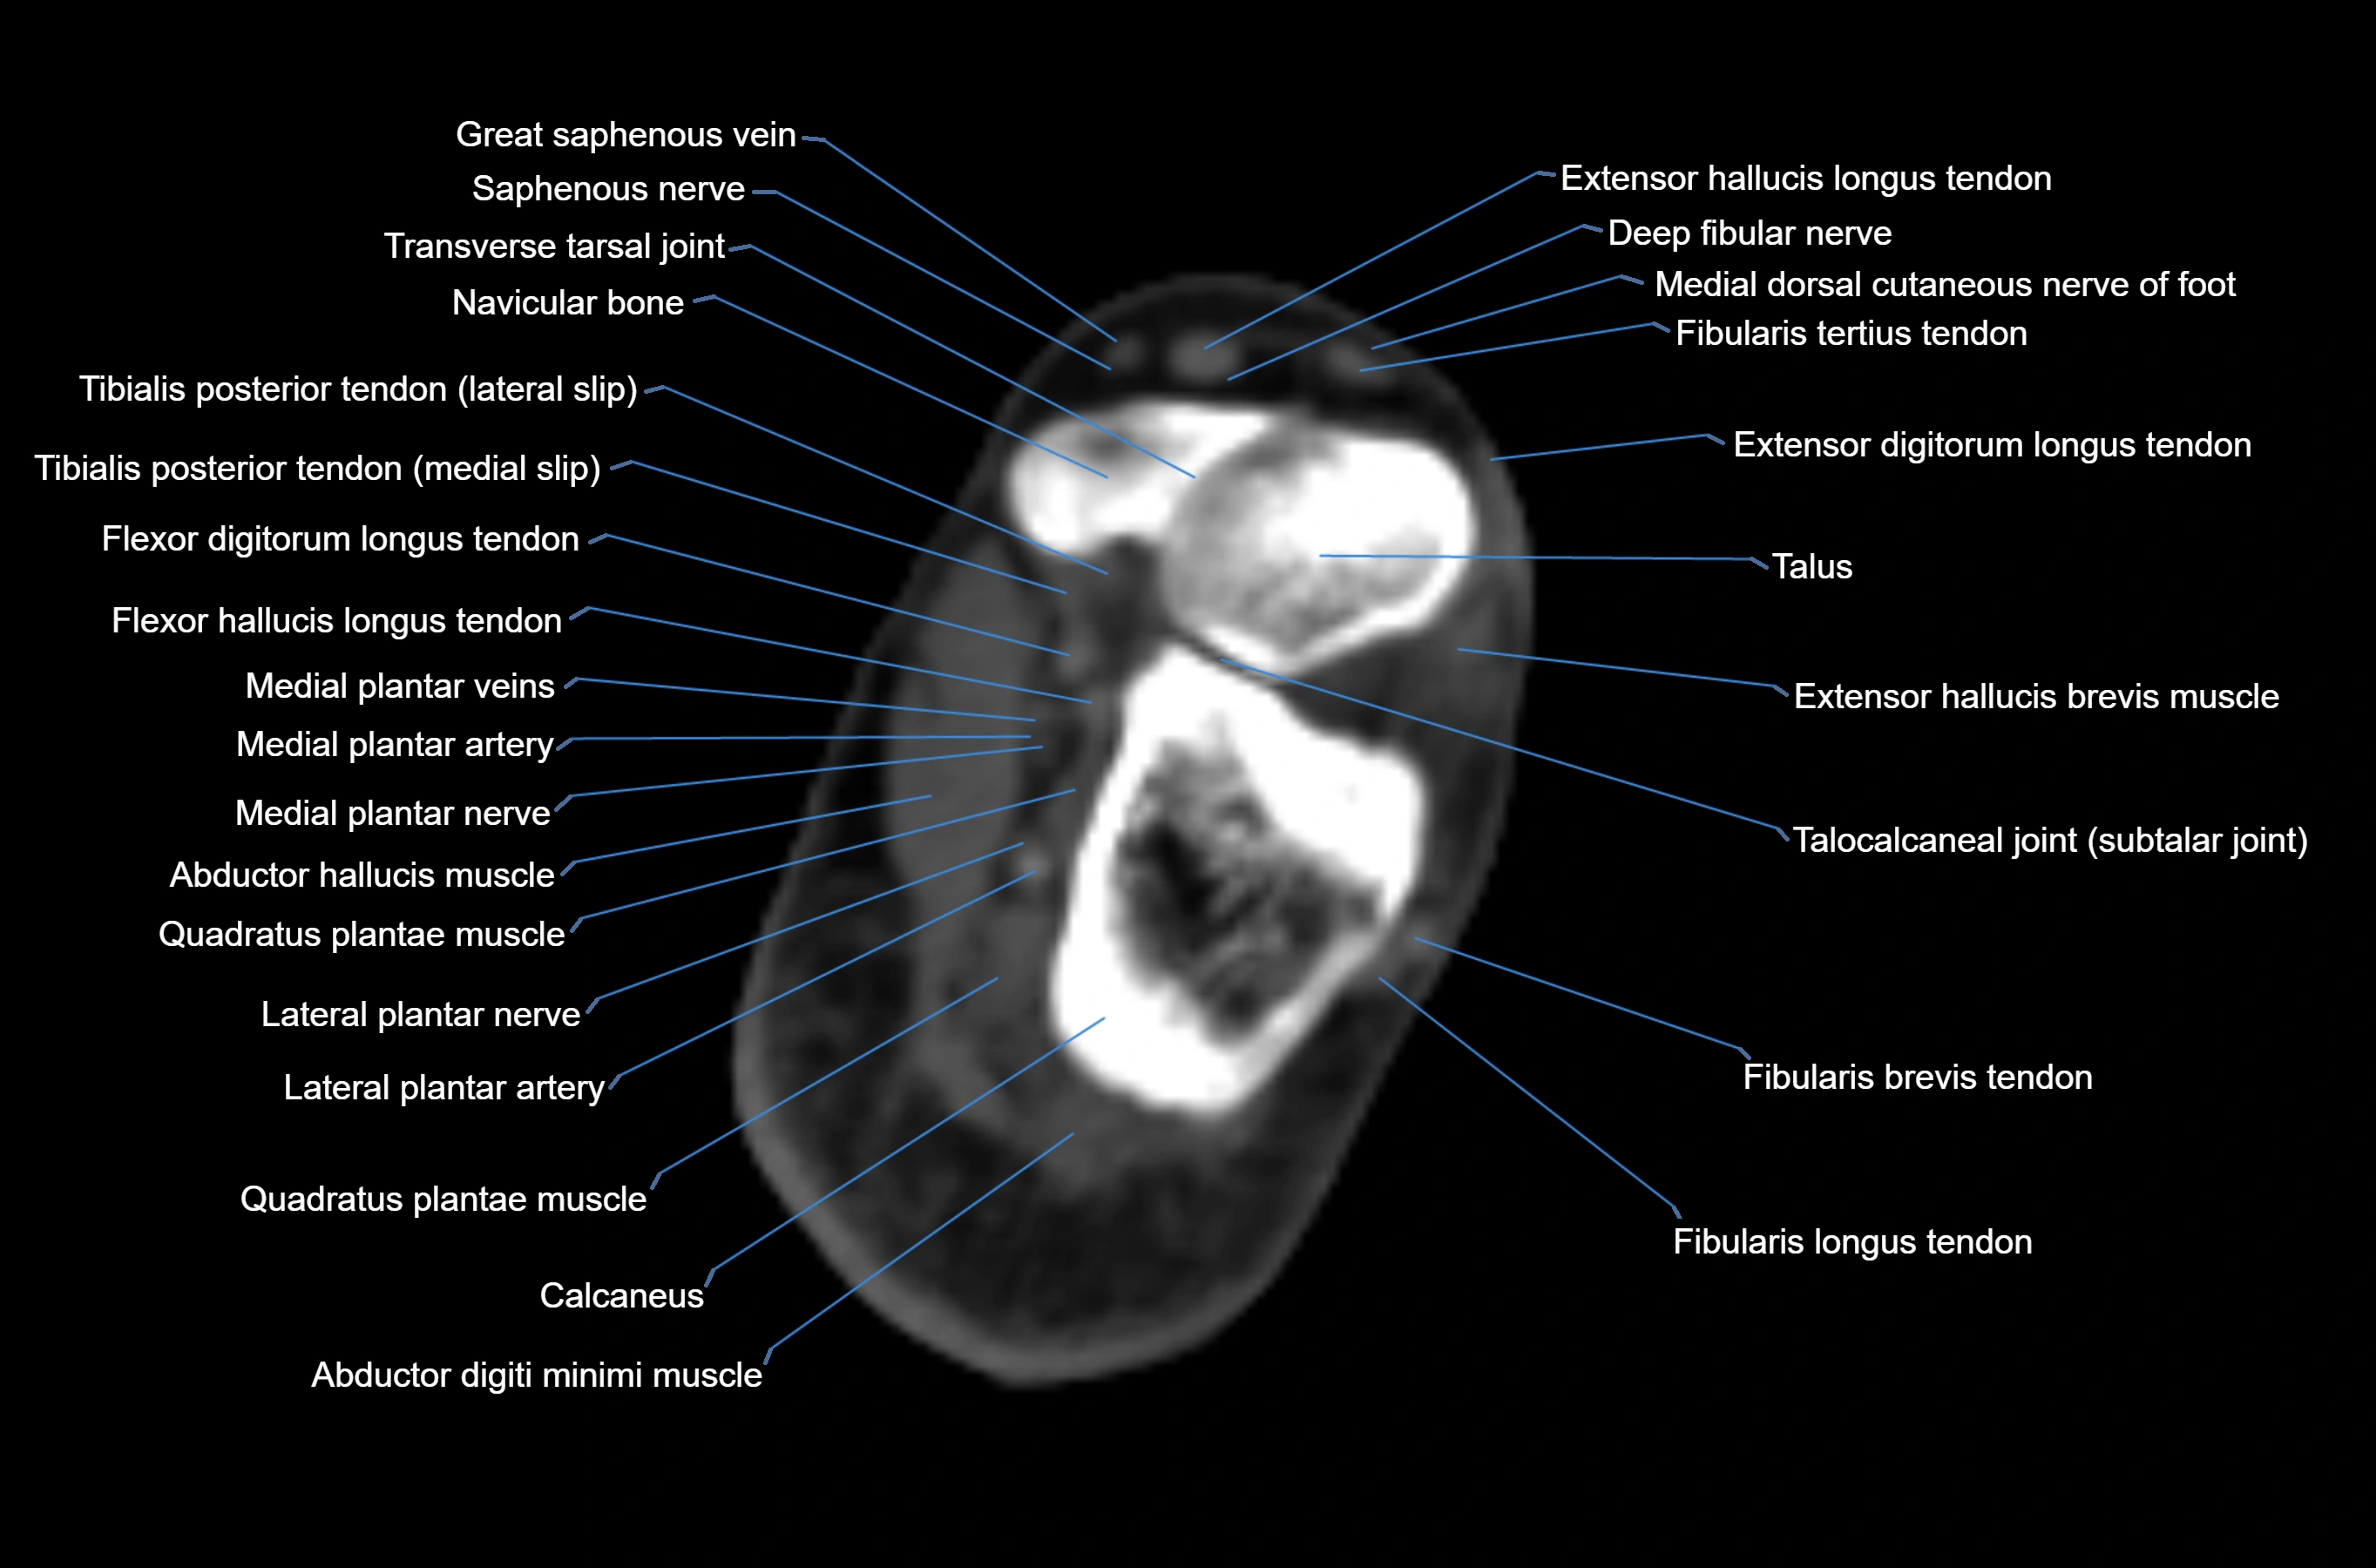

CT image